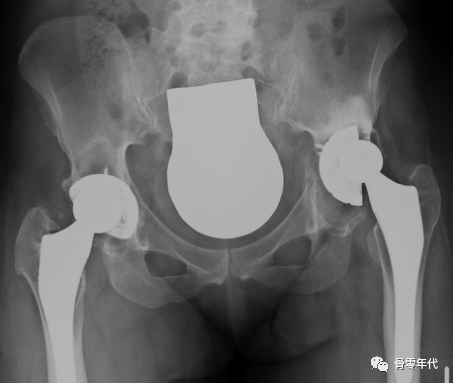

应用多孔钽假体重建Paprosky 3A缺损术的一例(左侧髋关节)的X线片:术前(左)、术后(中)和10年后(右)的正位X线片